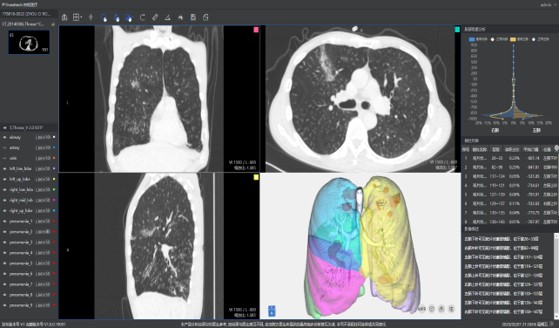

本系統(tǒng)是根據(jù)最新版新型冠狀病毒肺炎影像學(xué)診斷指南推出的針對新型冠狀病毒肺炎的輕量級輔助閱片工具。在公司原有AI輔助篩查系統(tǒng)的基礎(chǔ)上,聯(lián)合武漢協(xié)和醫(yī)院,依據(jù)新型冠狀病毒感染肺炎的影像學(xué)表征對原有AI產(chǎn)品做出升級,能夠快速對新冠肺炎疑似病例進行診斷篩查。目前疫情在短時間內(nèi)出現(xiàn)爆發(fā)式的就診需求,尤其是核心地區(qū),難以實現(xiàn)快速精準(zhǔn)的診斷。本系統(tǒng)能夠應(yīng)對可能出現(xiàn)的大規(guī)模病例篩查,有助于及時發(fā)現(xiàn)潛在病例,加強防控。

針對新冠肺炎的各種典型征象如:磨玻璃影(GGO)、斑片影、實性變化等,在短時間內(nèi)進行快速檢測,大大提高閱片效率,助力當(dāng)前新冠肺炎進行大規(guī)模影像篩查。

依據(jù)最新版新型冠狀病毒肺炎影像學(xué)診斷指南中對CT影像診斷的要求,聯(lián)手武漢協(xié)和醫(yī)院,大量高質(zhì)量的數(shù)據(jù)使柏視能夠提供準(zhǔn)確的處理結(jié)果。利用AI實現(xiàn)影像表征的自動定量化分析,通過病灶形態(tài)特征信息、密度信息等提示肺部病變;并能夠自動計算出疑似概率將病例進行分級分區(qū),方便醫(yī)生逐級篩查。

此次新冠肺炎傳播速度快,病情發(fā)展較為迅速,早期、進展期 、重癥期的影像表現(xiàn)有著明顯區(qū)別。本系統(tǒng)還具備對多次檢查結(jié)果進行對比分析的功能,提高診斷效率。同時,為更加方便的應(yīng)對當(dāng)前客戶需求,系統(tǒng)同時具有根據(jù)醫(yī)院的需求生成符合最新型冠狀病毒肺炎診斷指南的結(jié)構(gòu)化圖文報告的功能。